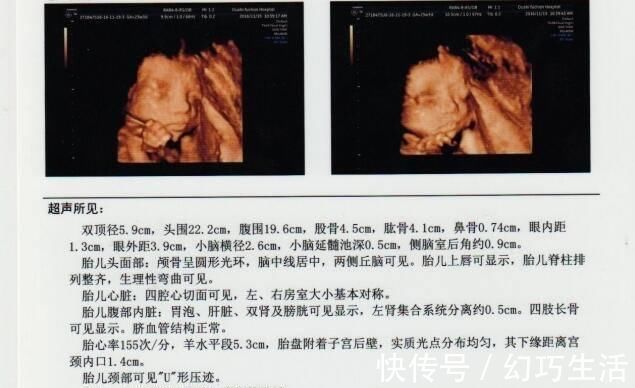

其实对孕妈来说,检查报告最不明确的应该是各个数据的意义,比如图示的双顶径5.9cm,这个双顶径是什么?5.9cm标准吗?对胎儿有哪些影响呢?所以说,只要明确了几个重要数据的意义,那检查报告对孕妈来说,看起来就会很容易了。

如图示,羊水平段5.3cm。这个羊水平段,也就是羊水深度,是指B超检查的最大羊水池的垂直深度,正常范围为3-8cm,小于3cm羊水过少,大于8cm羊水过多,过多多少都得重视。